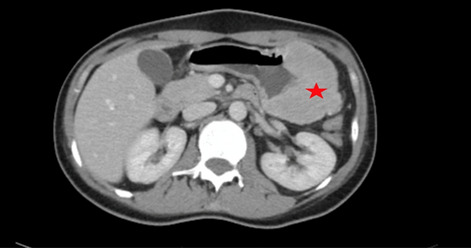

Result: The comparative analysis of the data shows a decrease in the number of presentations in ESU of AC cases during the pandemic, compared to the previous year, most often due to patients' fear of contacting the virus in the hospital environment. The median time between the onset of symptoms and the presentation in the ESU: 2020 – 14 days, 2019 – 5 days. Forms of moderate and severe AC predominated in the pandemic: GradeI—14.28%; GradeII—57.14%; GradeIII—28.57%. In 2019 GradeI—66.39%, GradeII—27.73%, GradeIII—5.88%. Laparoscopic cholecystectomy was attempted for all patients from the beginning, but the complications identified during surgery and severe forms led to a conversion rate in 2020 of 14.28%, compared to 5.88% in 2019. The severity of the cases is also observed in the postoperative complications encountered (perihepatic abscess Fig. 2. Figure 2, wound infection, bile leak; 2019—5.04%, 2020—23.21%), which required surgical reinterventions to solve them (2019: 2.52%, 2020: 10.71%). The number of deaths was significantly higher in 2020 (5.35%), compared to 2019 (0.84%).